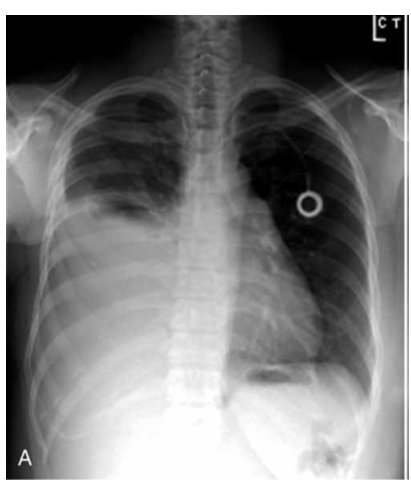

Um homem de 75 anos, com histórico de câncer de pulmão metastático, em tratamento quimioterápico, procura atendimento devido à dispneia progressiva e dor torácica leve há duas semanas. Ele não apresenta febre ou outros sinais infecciosos. No exame físico, observa-se murmúrio vesicular diminuído e macicez à percussão no hemitórax direito. Uma toracocentese diagnóstica revela líquido de aspecto sero-hemático com pH 7,2, glicose 45 mg/dL e citologia positiva para células neoplásicas. A radiografia de tórax está demonstrada a seguir.

Com base no relato e na radiografia apresentados, assinale a alternativa que indica a melhor abordagem terapêutica inicial para esse paciente.